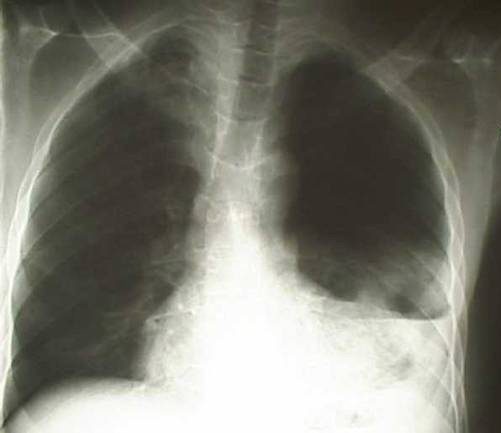

При гемотораксе определяется отставание пораженной стороны грудной клетки при дыхании, притупление перкуторного звука над уровнем жидкости, ослабление дыхания и голосового дрожания. При рентгеноскопии и обзорной рентгенографии легких выявляется коллабирование легкого, наличие горизонтального уровня жидкости или сгустков в полости плевры, флотация (смещение) тени средостения в здоровую сторону.